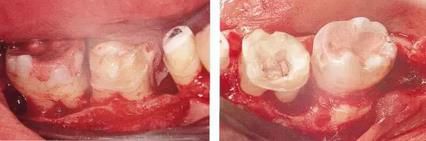

360截圖20170422101920025.jpg

▲圖7-2,3

▲圖7-2 齦瓣剝離后,可以看到右上3近中側(cè)沉積著大量牙結(jié)石。由于牙根接近而無法用刮匙除去

▲圖7-3  牙周外科處理后的愈合期狀態(tài)。右上2,3之間愈合形成了充分的角化齦。